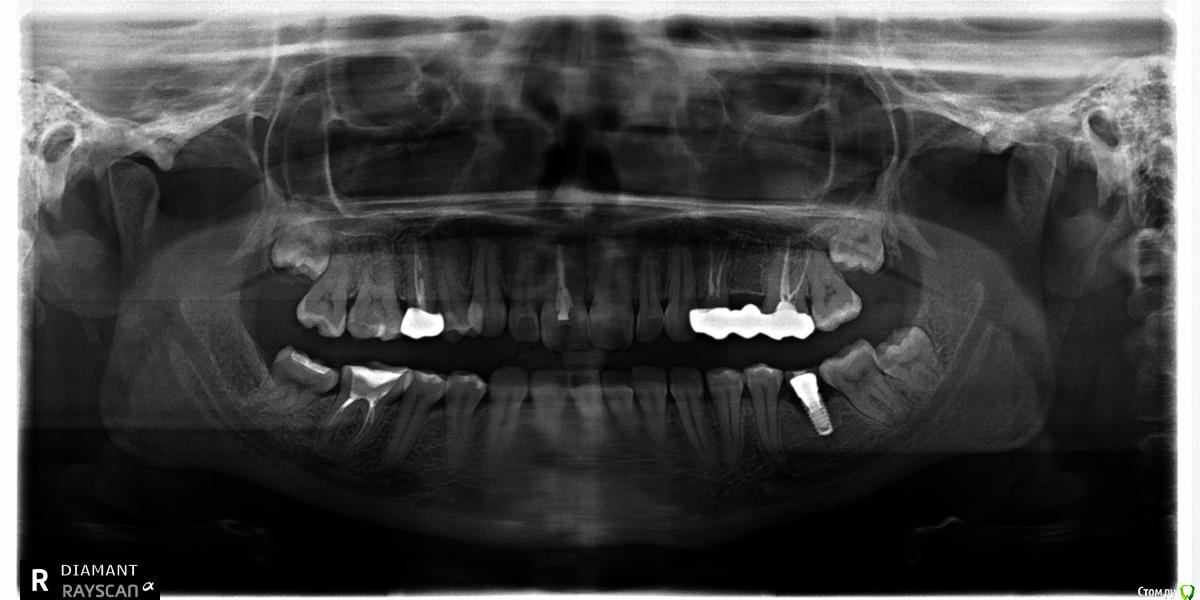

Нина86 Опубликовано 14 августа, 2019 Поделиться Опубликовано 14 августа, 2019 Здравствуйте! Проконсультируйте, пожалуйста, по поломке импланта. 5 лет назад поставила зубной имплант фирмы Megagen (диаметр 4 мм, длина 8,5 мм, Южная Корея, там и ставила).Месяц назад он сломался (сам имплант). На вопрос: "Почему же так произошло?" два стоматолога сказали, что не знают, просто импланты иногда (редко) ломаются. При внимательном рассмотрении панорамных снимков у нас с мужем возник вопрос, а не мог ли имплант сломаться из-за зачатка зуба мудрости, который давил на соседний зуб, а он, в свою очередь, на коронку импланта? Если это могло быть так, то нужно ли удалять зачаток зуба мудрости с той стороны, где имплант, перед установкой нового импланта или это можно сделать после его установки? И последний вопрос: можно ли устанавливать новый имплант в один день с удалением сломанного импланта? Снимки за 2017, март 2019 (до поломки импланта) и за июль 2019 (после поломки импланта) приведены ниже. Огромное спасибо! Ссылка на комментарий

колесников Опубликовано 15 августа, 2019 Поделиться Опубликовано 15 августа, 2019 Почему сломался? Можно только предполагать,но вероятно тут несколько предпосылок к этому было.Во первых ,как видно на снимке,стенка импланта довольно тонкая. Хотя диаметр 4.0 пригоден для установки в области моляров,в данном случае нагрузка оказалось запредельна для стенки такой толщины и для этого сплава . Во вторых ,почему сломался,ведь там внутренний конус? Да на коническом соединении мы получаем минимальную нагрузку на внутреннюю стенку шейки импланта и проблема перелома должна нас не волновать. Но! На корейских системах не оригинальный конус морзе,другой градус,вероятно градус имеет значение.В третьих,так же по снимку можно предположить ,что абатмент платформой «не сел» ,возможно не оригинальный,не правильное распределение нагрузки,как итог микролюфт и переломВ четвёртых,перед фиксацией коронки заметно что имплант более 1/3не в кости. Перелом проходит по костной границе . Вероятно были избыточные боковые нагрузки что привело к микролюфту и перелом произошёл по границе интегрированного с неинтегрированым. Ссылка на комментарий